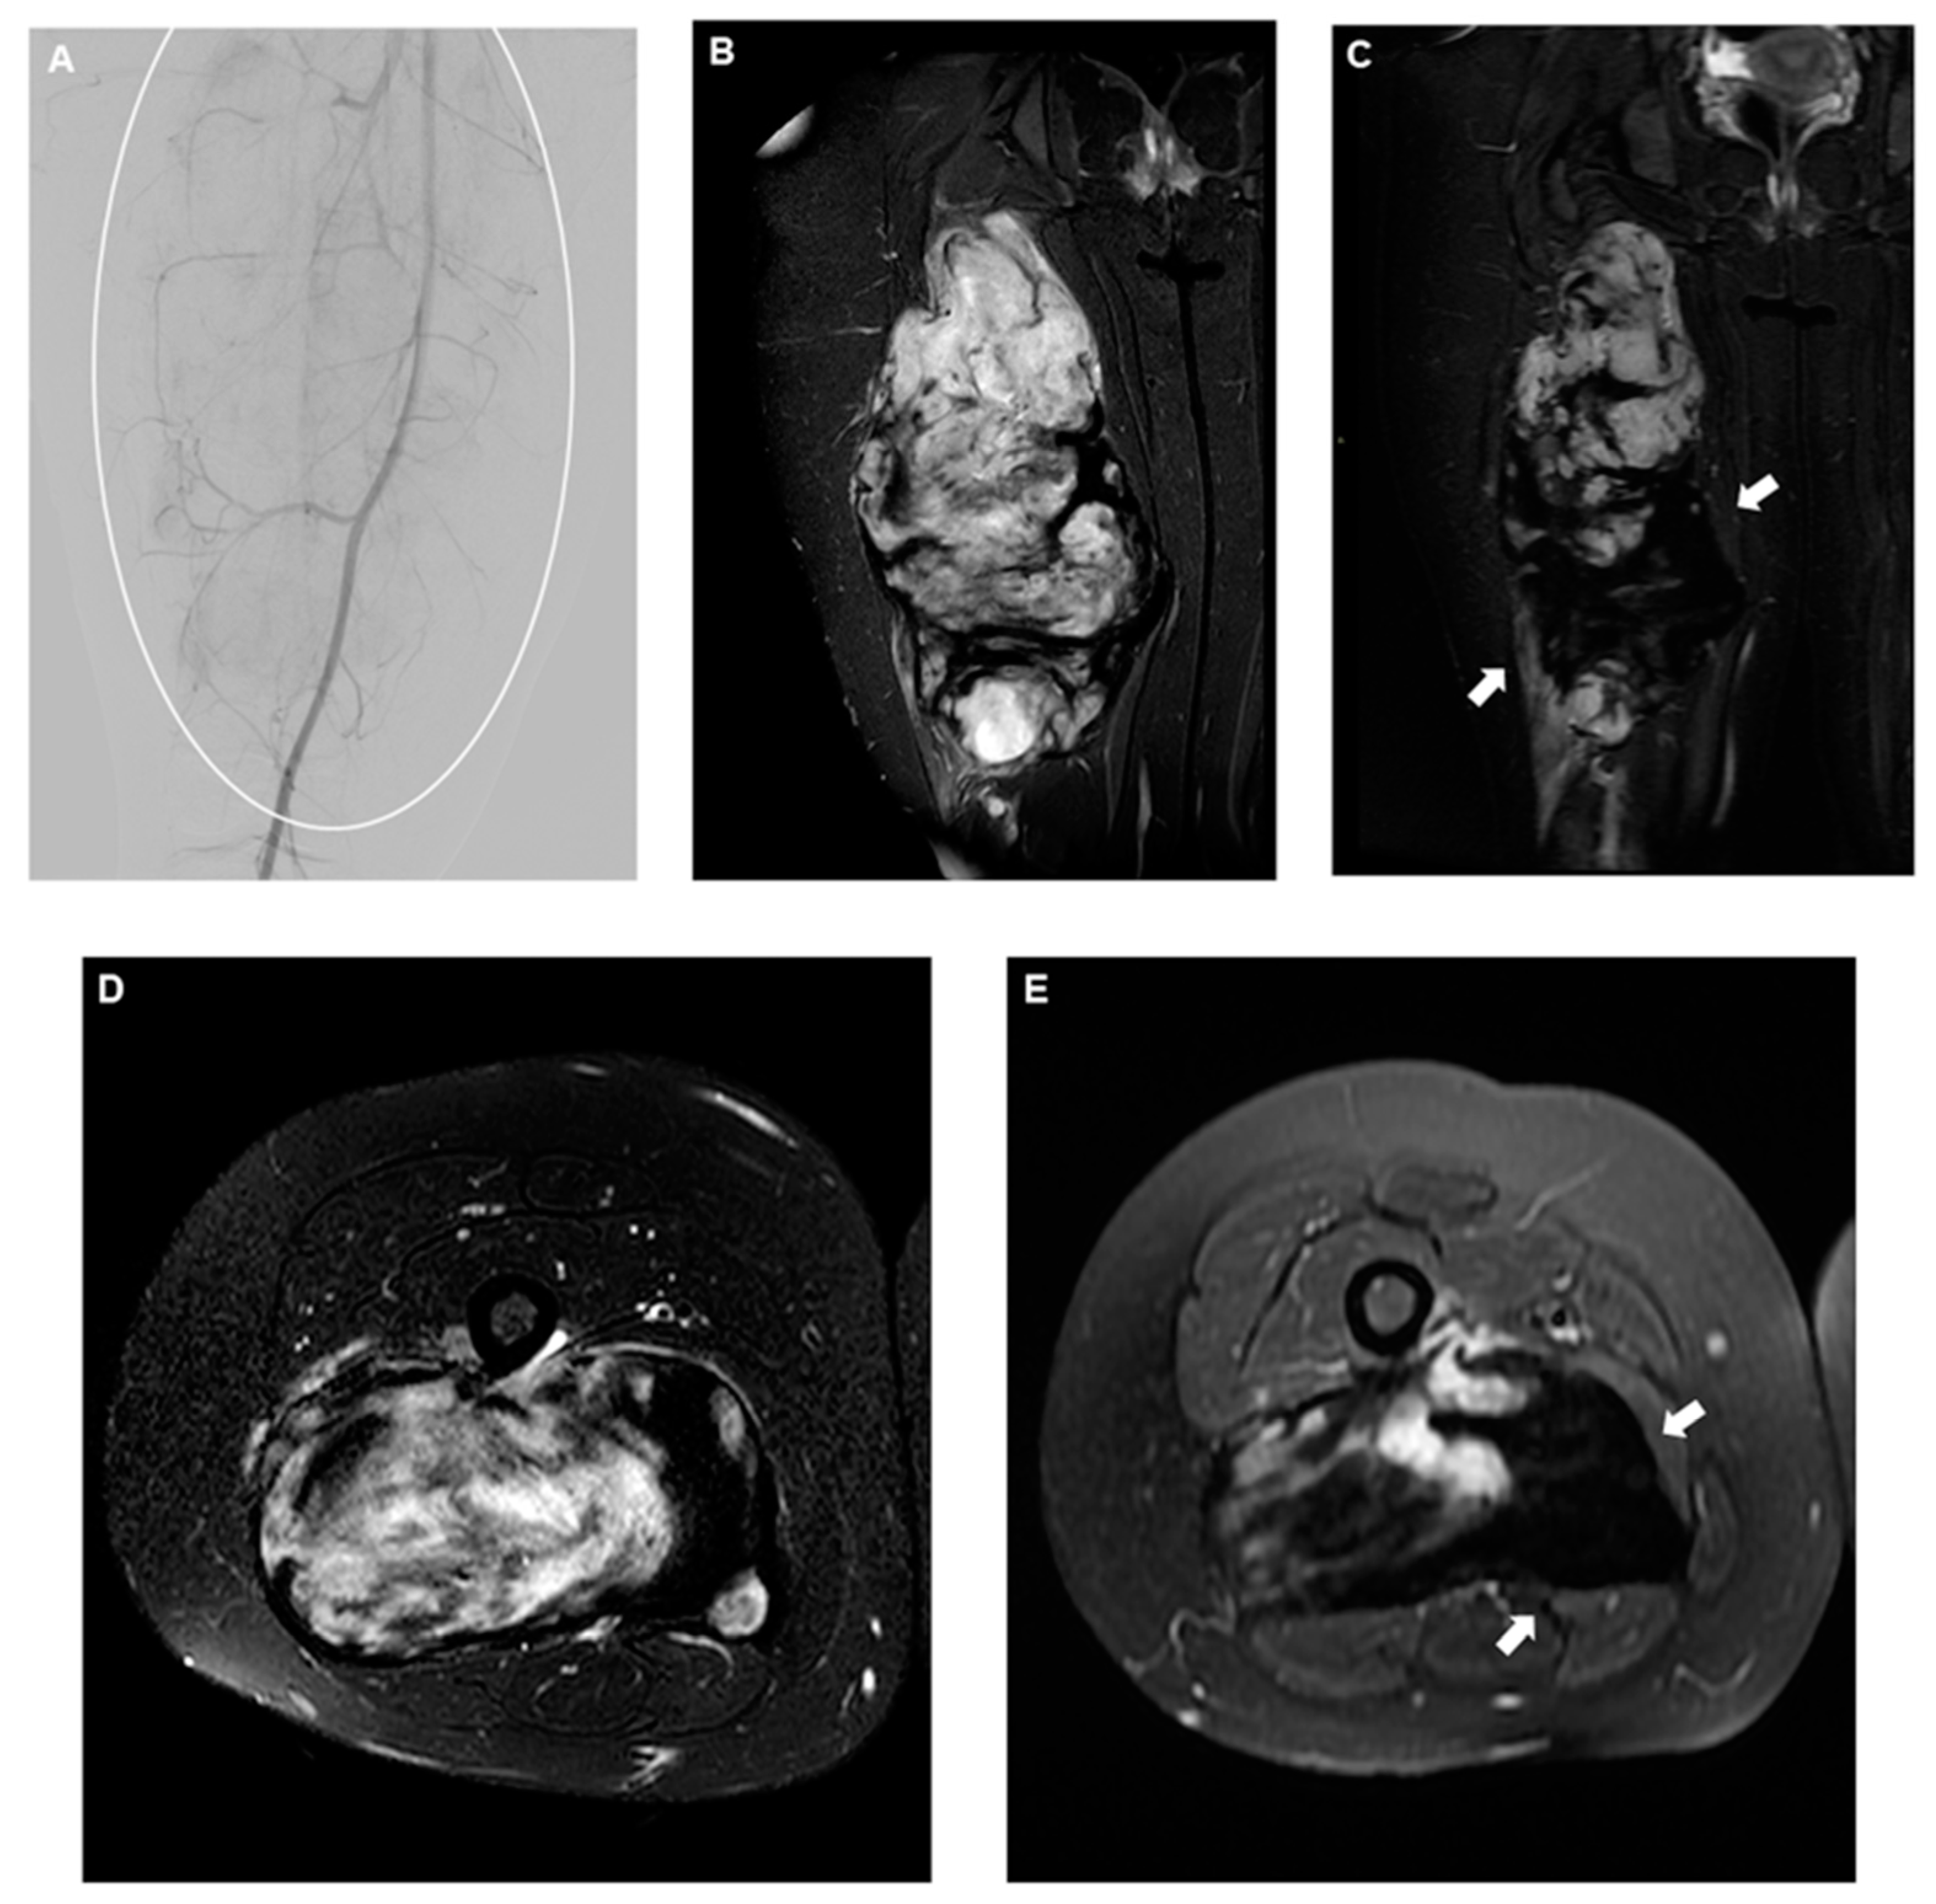

2.8.3. Desmoid Fibromatosis

2.8.4. Degenerative